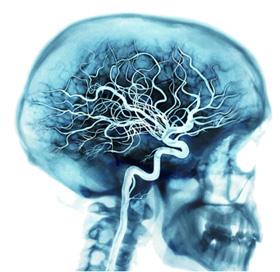

養份供應

大腦的養份是由體內其中最龐大、最密集的血管網絡所提供。 每下心跳,動脈會輸送百分之 20 至 25 的血液到腦部,而以 10 億計的腦細胞平均消耗血液中約 20% 的氧氣和養份。…